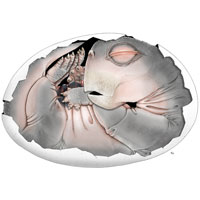

Перед вами фотография среза мышечной ткани собаки, которая страдала паразитарным заболеванием — гепатозоонозом. На срезе видны многочисленные мышечные волокна (розового цвета с фиолетовыми ядрами) и многослойное округлое образование, расположенное в самом центре. Это циста, внутри которой развивается возбудитель болезни — одноклеточный паразит Hepatozoon americanum из группы споровиков (Apicomplexa), к которой относятся также всем известные токсоплазма и малярийный плазмодий.

Паразиты активно проникают внутрь макрофагов (с помощью апикального комплекса органелл) и начинают формировать ту самую цисту, которую вы видите на фотографии. В самом ее центре находится «плененный» макрофаг, у которого хорошо заметно смещенное к краю ядро с ядрышком. Но где же сам гепатозоон? Паразит занимает весь остальной объем клетки макрофага, потеснив его ядро к периферии. На фотографии видна стадия развития гепатозоона, когда он только приступает к внутриклеточному размножению (стадия шизонта): его ядро уже многократно поделилось, но еще не произошло образование оболочек клеток вокруг дочерних ядер. Поэтому на фото нельзя различить отдельные клетки гепатозоона внутри макрофага. Зато хорошо заметна многослойная оболочка цисты, которая дала этой структуре название циста-«луковица» (onion skin cyst). Гепатозоон вызывает в макрофаге усиленный синтез мукополисахаридов, которые слоями откладываются на поверхности клетки, делая ее похожей на луковицу. Предположительно, такая многослойная циста защищает гепатозоон от иммунной системы хозяина, что необходимо на этой стадии. Цисты-«луковицы» имеют размер от 80 до более чем 300 мкм.

Развитие H. americanum в скелетных мышцах. A — «циста-луковица» (O): содержит клетку хозяина с ядром (показано короткой стрелкой) и большим ядрышком. В клетке хорошо заметен трофозоит (показан длинной стрелкой). Многослойная оболочка цисты состоит из мукополисахаридов, синтезированных инфицированной клеткой хозяина. B — ранний этап развития шизонта (показан короткими стрелками). C — шизонт с хорошо дифференцированными мерозоитами. D — гранулёма — скопление макрофагов в очаге воспаления, многие с паразитами внутри (показаны короткими стрелками). Длина масштабного отрезка: 50 мкм (A и D), 25 мкм (B и C). Фото из статьи S. A. Ewing, R. J. Panciera, 2003. American Canine Hepatozoonosis